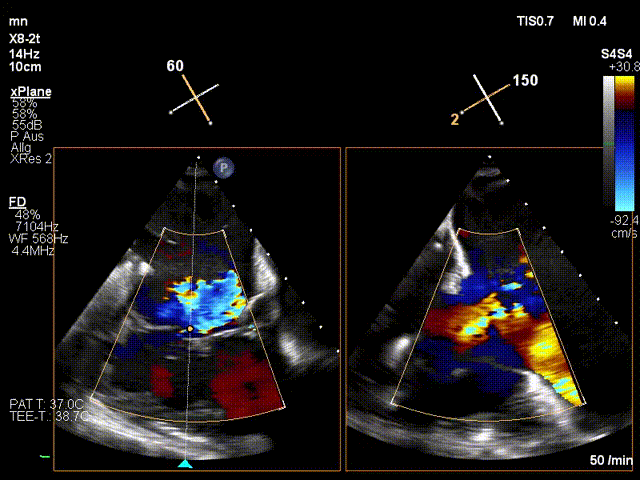

近日,德國慕尼黑大學(xué)Jörg Hausleiter教授團(tuán)隊(duì)成功應(yīng)用LuX-Valve Plus經(jīng)血管三尖瓣置換系統(tǒng)救治了一例因三尖瓣大量反流導(dǎo)致的右心衰竭患者,術(shù)后超聲顯示人工三尖瓣位置固定滿意,瓣架穩(wěn)定,無反流和瓣周漏?;颊咴谑中g(shù)室即刻拔除氣管插管,血流動(dòng)力學(xué)改善顯著,LuX-Valve Plus經(jīng)血管三尖瓣置換系統(tǒng)的治療效果優(yōu)異。

手術(shù)在全麻狀態(tài)下進(jìn)行。在加拿大圣保羅醫(yī)院的Anson Cheung教授的指導(dǎo)參與下,術(shù)者采用經(jīng)右側(cè)頸靜脈入路的方式將輸送器送入患者心臟內(nèi),在TEE及DSA引導(dǎo)下調(diào)整輸送器頭端角度,使得輸送器與三尖瓣瓣環(huán)平面垂直。在輸送器進(jìn)入右心室后釋放室間隔錨定裝置,而后釋放瓣葉夾持件(2個(gè)耳片結(jié)構(gòu))成垂直狀態(tài)。在TEE及DSA確定夾持件固定至三尖瓣葉根部且位于右室側(cè)后釋放人工瓣心房側(cè)盤片。隨后調(diào)整瓣膜同軸性以及室間隔錨定件位置(貼合室間隔),前推藏針管并固定,進(jìn)而釋放室間隔錨定裝置,并再次確認(rèn)瓣膜位置、穩(wěn)定性及同軸性,合攏輸送鞘后撤出輸送器,完成LuX-Valve Plus人工三尖瓣瓣膜的植入。

LuX-Valve Plus經(jīng)血管三尖瓣置換系統(tǒng)本次“出海”圓滿完成,術(shù)后Jörg Hausleiter教授對(duì)LuX-Valve Plus經(jīng)血管三尖瓣置換系統(tǒng)的器械性能和治療效果大為稱贊,認(rèn)為LuX-Valve Plus的手術(shù)體驗(yàn)非常好。術(shù)后即刻超聲顯示三尖瓣反流消失,血流動(dòng)力學(xué)改善顯著,患者恢復(fù)快。Anson Cheung教授也肯定了LuX-Valve Plus術(shù)中操作的便捷性,認(rèn)為LuX-Valve Plus容錯(cuò)率高,對(duì)術(shù)中影像的依賴較小,后期希望可以更多的應(yīng)用LuX-Valve Plus三尖瓣置換系統(tǒng)于臨床實(shí)踐,讓更多的三尖瓣重度反流患者盡早獲益,改善預(yù)后。